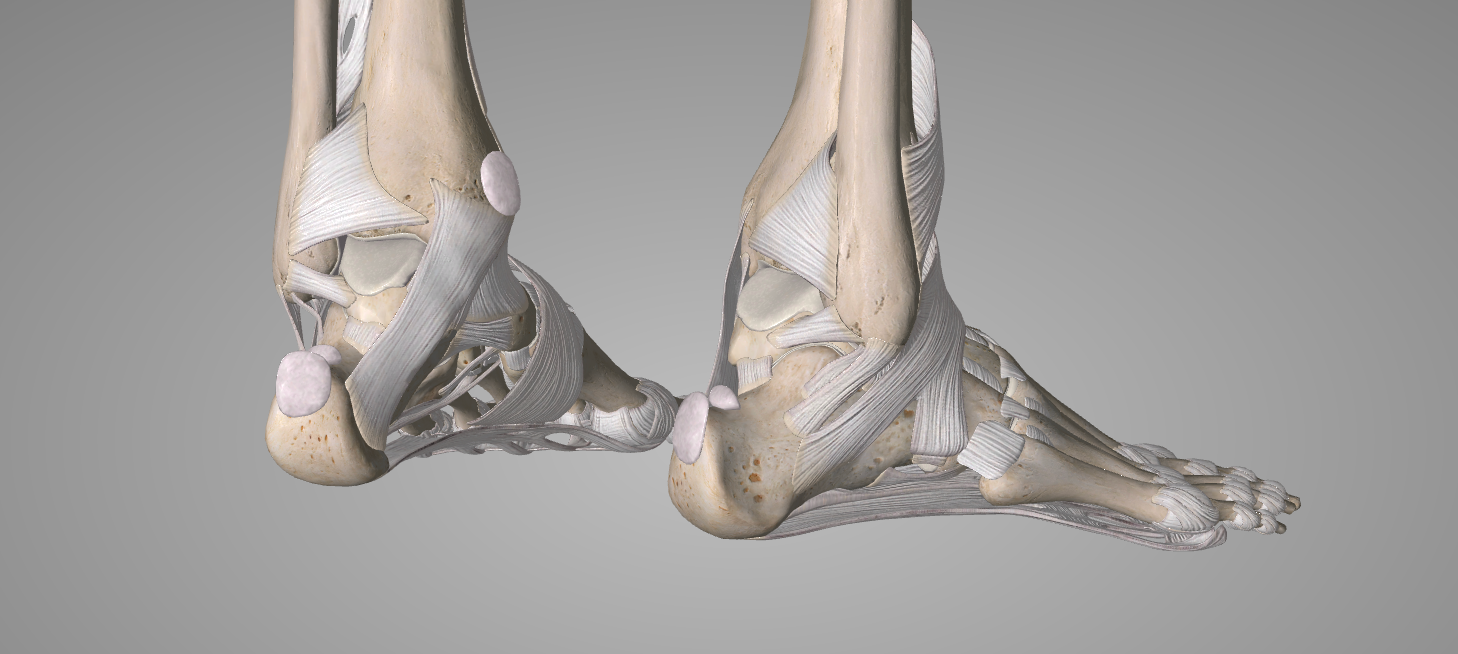

Cualquier ligamento del cuerpo es susceptible de sufrir un esguince, pero concretamente en el tobillo el más habitual es el esguince lateral externo en el que se fuerza el pie a una inversión (el pie gira hacia adentro) comprometiendo ligamentos que conectan las articulaciones del hueso peroné con el astrágalo y el calcáneo:

- Ligamento peroneoastragalino anterior (LPAA)

- Ligamento peroneocalcáneo (LPC)

- Ligamento peroneoastragalino posterior (LPAP)

- Ligamento talocalcáneo lateral (conecta astrágalo y calcáneo)

El esguince medial interno afecta al ligamento deltoideo, que es un complejo ligamentoso grueso y fuerte en la cara interna del tobillo, formado por 3 fascículos; (tibioescafoideo, tibiocalcáneo y tibiotalar posterior superficial), este complejo ligamentoso conecta la tibia con el astrágalo, el calcáneo y el escafoides, por lo que estabiliza tanto la articulación tibioperoneoastragalina como otras articulaciones del retropié.

ARTICULACIONES IMPLICADAS:

- Tibiotalar medial (tibiotalar deltoidea)

- Tibiocalcánea

- Tibioescafoidea

Afecta a los ligamentos que mantienen unidos la tibia y el peroné en su parte distal y son los siguientes:

- Ligamento tibio-peroneo anterior inferior

- Ligamento tibio-peroneo posterior inferior

- Ligamento interóseo o membrana interósea distal